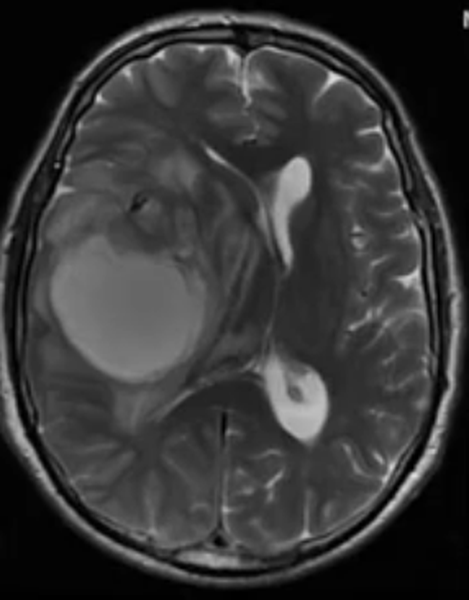

Медицинские аспекты и диагностика субдуральной гигромы мозга